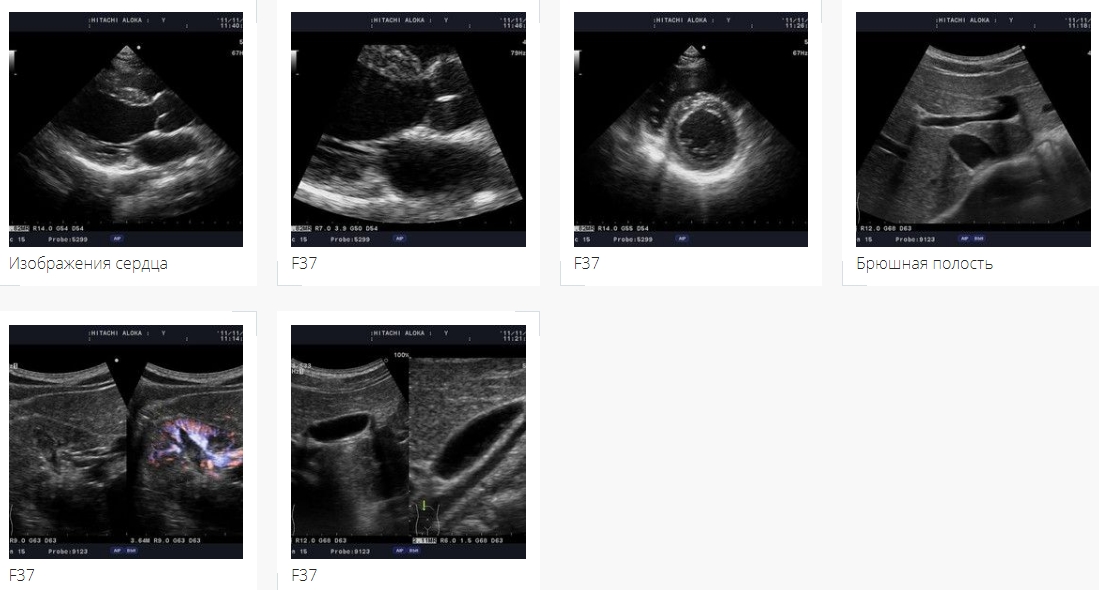

F37 - Цветной полностью цифровой ультразвуковой сканер высокого класса для общих исследований, акушерства, гинекологии и кардиологии и др

Ультразвуковой сканер Hitachi Aloka F37 - гармоничный продуманный внешний облик и экспертные возможности визуализации, ориентированные на ежедневное использование.